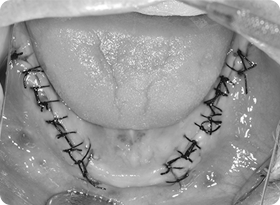

03뼈이식 진행(1차수술)

잇몸을 최소절개하여 부족한 잇몸뼈를 대신해 뼈이식를 살포한 후 뼈이식재를 보호하기 위한 보호막을 덮고 잇몸을 단단히 봉합합니다. 이후 잇몸과 이식한 뼈가 아무는데까지 3~6개월 가량 기다립니다.